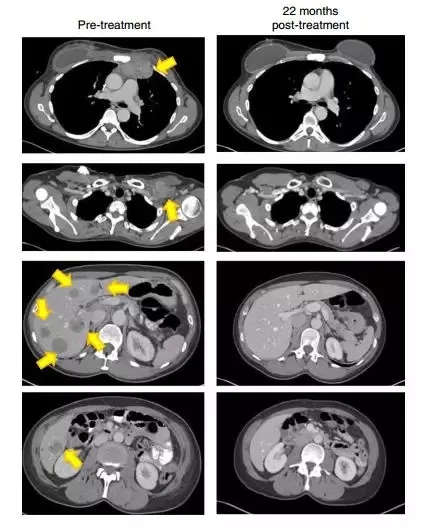

一名患有轉移性鱗狀細胞癌并接受了多種聯合化療方案,包括順鉑,長春新堿和博來霉素,然后用吉西他濱加順鉑聯合放療。隨后發現轉移,包括主動脈旁,雙側肺門,顱下和髂骨部位(圖1A和1C)。治療后,她在所有疾病部位都完全消退(圖1A和1C)。

另一患者患有轉移性腺癌。她的原發性腫瘤對化放療無效。隨后轉移到更多的腹膜后淋巴結和肝臟表面,在TIL治療前,她在腹膜后,腹壁,旁系,肝旁和盆腔部位有腫瘤進展(圖1B和1d)。在治療后,出現完全的臨床緩解(圖1B和1d)。

2018年,《自然醫學》(Nature Medicine)上發表的一份報告描述了在用對4種突變蛋白(SLC3A2,KIAA0368,CADPS2和CTSB)的TILs治療的患者中成功治療化學難治性激素陽性轉移性乳腺癌。在報告發表時,反應已經持續進行了22個月以上,并且患者在4年后仍然沒有疾病。

22個月后,這名患者的腫瘤(黃色箭頭)消失得無影無蹤(圖片來源:《Nature Medicine》)